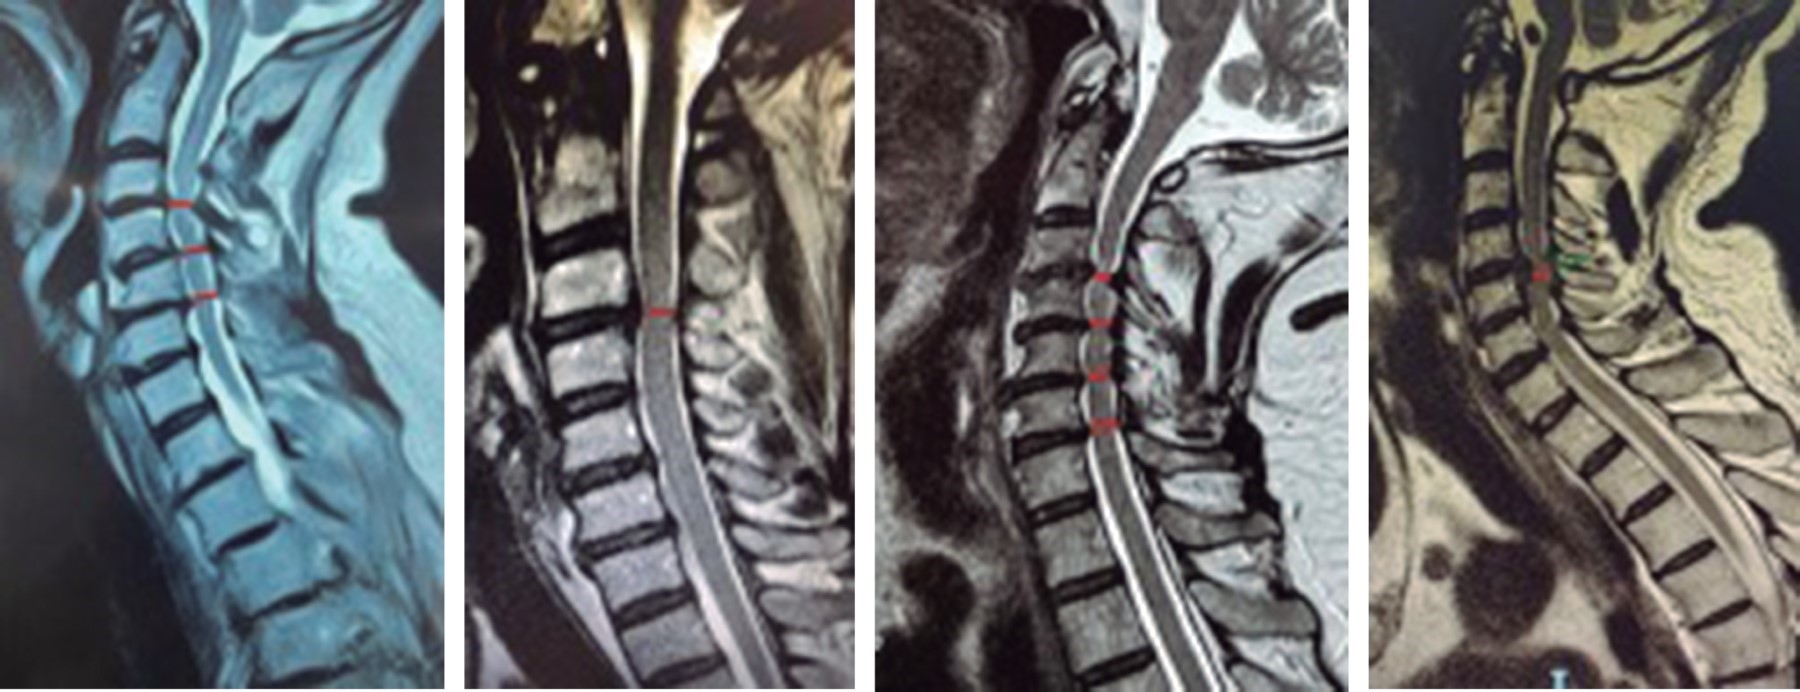

Cervical myelopathy is induced by static factors (space available for the spinal cord), dynamic factors (range of intervertebral movement) or a combination of both.11 Within the static factors we cite in this work the content and container, and its implications direct towards the cervical spinal cord due to the degenerative changes between each one (Figure 1), documented by a simple T2-weighted magnetic resonance study in sagittal section.

We suggest a simple, practical and reproducible classification system based on simple T2-weighted magnetic resonance imaging in sagittal section, where the narrowest diameter of C2-C7 is the one considered for this measurement (Figure 3). We propose that these measurements are always correlated with Nurick, as well as to individualize each patient for their correct treatment.